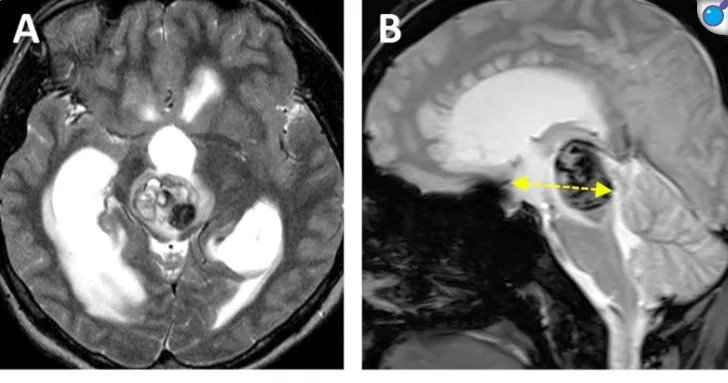

爱丽丝的病灶位于腹侧中脑中线区域,体积为10.7立方毫米,深度为42.5毫米,肿瘤偏侧角度为11.6度(图a, b)。

图a、b为术前MRI图像,显示被归类为"中央区病变"的中脑海绵状血管瘤出血。图中黄色虚线标示了肿瘤的深度(42.5毫米)。